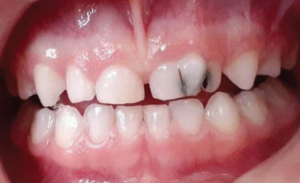

Figure 8: Carious enlarged crown of a geminated primary upper left central incisor

Gemination

Gemination results from a single tooth attempting to divide. It presents as a bifid crown with a single root and root canal.[22] Unlike fusion, gemination does not reduce tooth count.[23] Deep grooves increase caries risk. Treatment may include sealants, restorations, or orthodontic correction.[23]

Clinically, geminated teeth can cause aesthetic concerns, spacing issues, and malocclusion. Depending on its impact, treatment may include sealants, restorations, orthodontic correction, or extraction in severe cases.[23]